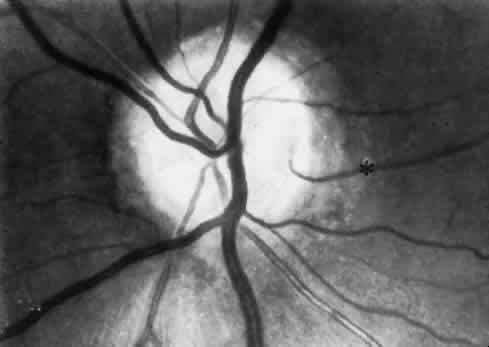

| For the purpose of this discussion, the intraocular circulation is divided